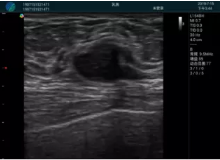

清晰顯示腺體內低回聲快影,邊界清晰,包膜較光滑

確定進針路徑并實時監(jiān)測抽吸針與腫塊位置關系

抽吸針進入腫塊內部進行旋切

抽吸過程中可見腫塊明顯縮小,并根據腫塊位置改變針道位置

抽吸旋切后再進行超聲復查,原腫塊區(qū)域未見殘留組織及出血